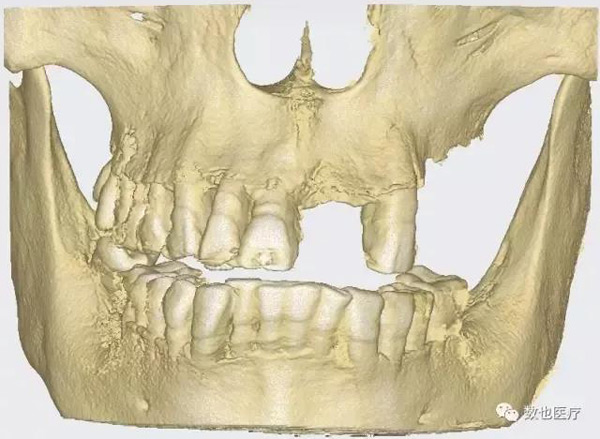

患者上颌骨条件较差,拔牙后存在较多的拔牙窝。考虑做即刻修复需要较好的初期稳定性,根据患者颌骨情况,计划种植6颗cortex种植体,避开骨缺损区域,远中两颗倾斜避开上颌窦。